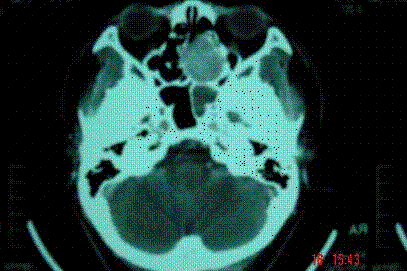

问题 病历摘要: 患者男,37岁,因右鼻塞伴涕中带血4个月入院,患者4个月前始右鼻塞,为间断性,偶有涕中带血,时有流脓性分泌物,并症状渐渐加重。但发病以来患者无头痛、面部麻木和疼痛,无复视及流泪,张口正常。检查:右侧鼻腔总鼻道可见表面光滑、质中、粉红色肿物,触之不易出血。鼻咽黏膜光滑,未见新生物和黏膜糜烂。颈部未及淋巴结肿大。 假如该肿瘤非目前状态,而是已侵犯颅底,如采用鼻窦进路切除该肿瘤,需注意些什么?